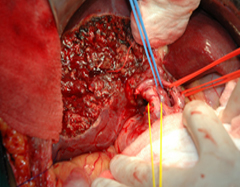

Intraoperative photo showing radical resection

Removal of Cancer Gallbladder